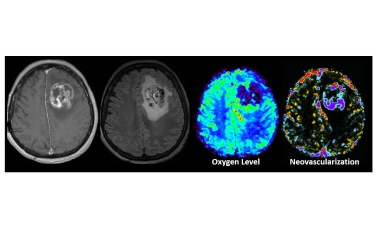

Studie der Karl Landsteiner Privatuniversität für Gesundheitswissenschaften belegt partielle Überlegenheit Künstlicher Intelligenz und physiologischer Bilddaten bei der Klassifikation von Hirntumoren.